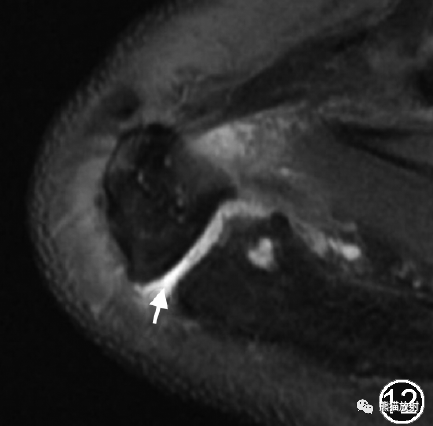

肩峰小骨可以不稳定,其软骨结合处或假关节下缘还可有骨刺形成,引起与肩袖的撞击。在MRI上当软骨结合处出现液性高信号时常提示肩峰小骨不稳。软骨结合处还可出现硬化、软骨下囊变及骨髓水肿。

图12 肩峰小骨的MR图像。肩关节MR平扫横断面脂肪抑制T2WI示肩峰小骨,其软骨结合处呈高信号(↑),锁骨远端可见囊变